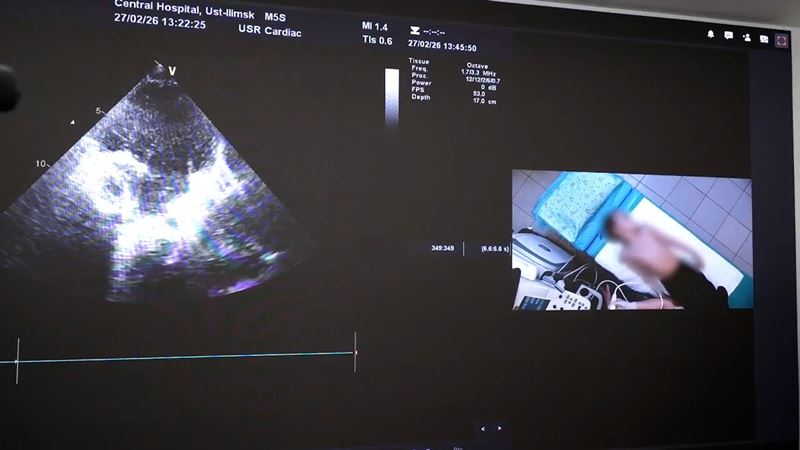

Это специализированное пространство, оснащенное современным оборудованием для проведения телемедицинских консультаций и анализа данных в сфере педиатрии. Техника обеспечивает передачу видеосигнала от диагностического оборудования с высокой точностью, что критически важно для постановки верного диагноза. Система также дает возможность проводить мониторинг состояния реанимационных пациентов по данным прикроватных мониторов, осуществлять дистанционные консилиумы и транслировать видео из операционных для консультативной поддержки при проведении сложных хирургических вмешательств. К работе в новом формате привлекли 19 специалистов больницы по различным профилям. Планируется, что ежегодно они будут проводить до двух тыс. дистанционных консультаций.